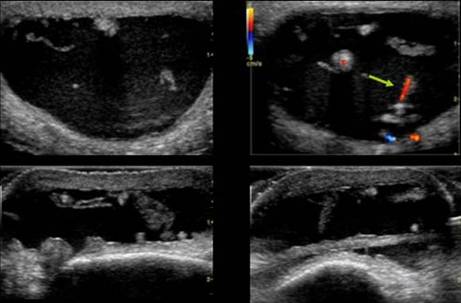

CHIST MUCOID INTRANEURAL AL NERVULUI ULNAR

Parestezii de lunga durata a degetelor 4 si 5

Structura chistica ce disociaza filetele nervoase → cu hiperemie in perinerv →

Pe IRM se evidentiaza hipertrofie nervoasa in T2 si prinde contrast in periferia chistului in T1